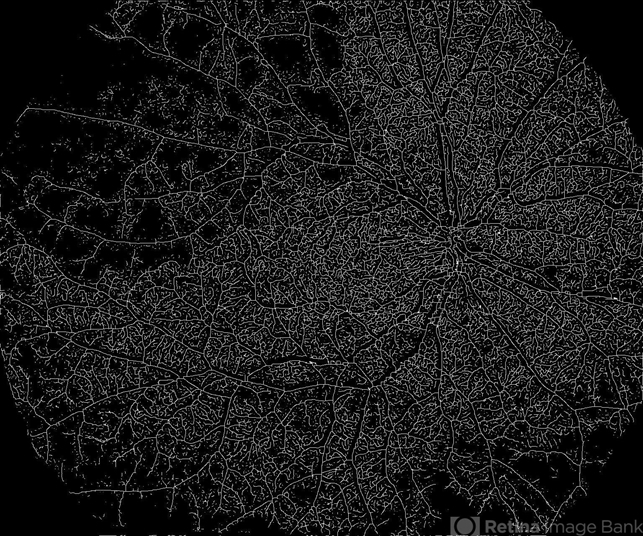

- retina, branch retinal vein occlusion (BRVO), nonproliferative diabetic retinopathy

TOWARDPI BMIZAR – 400KHZ FULL RANGE SS-OCTA - Description

- Ultra-Widefield OCT Angiography of a 77-year-old woman with ischemic occlusion of the superior temporal branch of the central retinal vein with non-proliferative diabetic retinopathy.